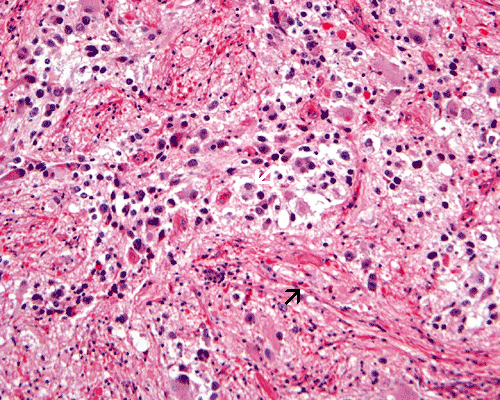

Desmoplastic infantile ganglioma: The collagenous fibers are highlighted by the arrow.